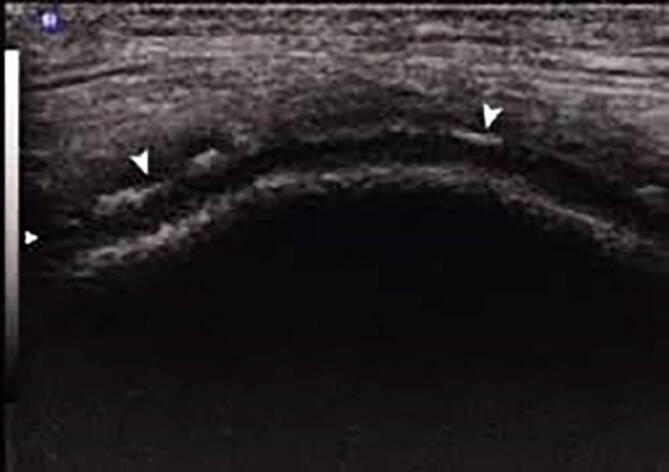

The presence of a crowned dens syndrome or calcium pyrophosphate crystals in the synovial fluid in patients with pain, swelling or sensitivity of the joints (entry criterion) is sufficient for the classification as CPPD disease, where the symptoms cannot be completely explained by another rheumatic disease (exclusion criterion). If these symptoms are not present, a count of more than 56 points based on weighted criteria comprised of clinical features and the results of laboratory and imaging investigations can be included for classification as a CPPD disease. These criteria had a sensitivity of 92.2% and a specificity of 87.9% in the derivation cohorts (190 CPPD cases and 148 mimics), whereas the sensitivity was 99.2% and the specificity 92.5% in the validation cohorts (251 CPPD cases and 162 mimics).

关节疼痛、肿胀或敏感的患者(纳入标准)出现冠状突综合征或滑液中有焦磷酸钙晶体,足以归类为CPPD疾病,前提是症状不能完全由另一种风湿性疾病解释(排除标准)。如果不存在这些症状,则根据由临床特征以及实验室和影像学检查结果组成的加权标准,得分超过56分可归类为CPPD疾病。这些标准在推导队列(190例CPPD病例和148例模拟病例)中的敏感性为92.2%,特异性为87.9%,而在验证队列(251例CPPD病例和162例模拟病例)中的敏感性为99.2%,特异性为92.5%。